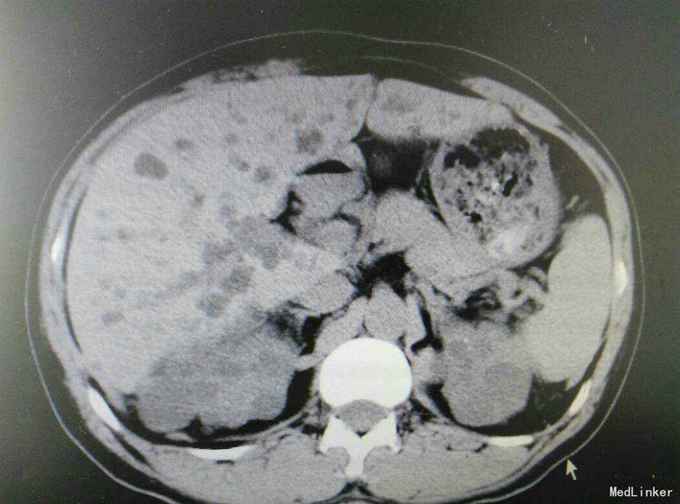

多囊肾合并双肾结石并积水

肾结石 多囊肾 多囊肝

患者47岁,男,因‘’腰痛伴、血尿伴发热7天‘入院。 患者既往有‘高血压’病史多年,7天前无明显诱因出现腰痛,随后出现肉眼血尿,为程肉眼血尿,当天晚上出现发热,最高体温38.6摄氏度,予以对症处理后,发热可退去,但症状反复,患者为求进一步进一步治疗遂来我院。

多囊肾,双肾结石,多囊肝,高血压